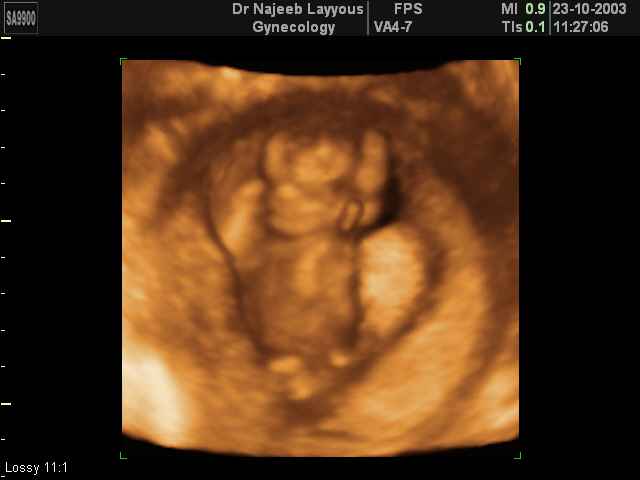

3D First Trimester Ultrasound Scan Photos